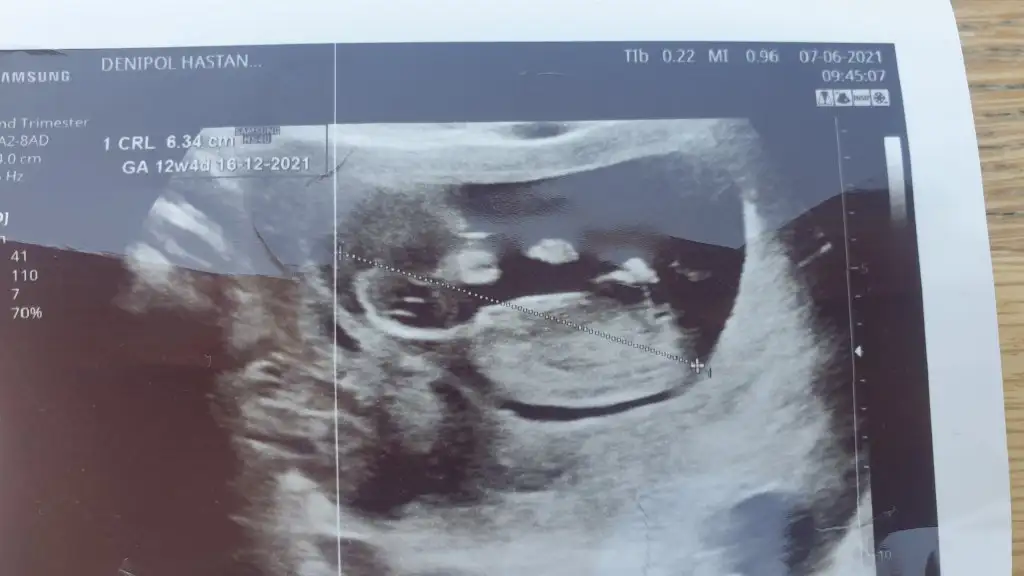

Selamlarr burdan da sorayım dedim Ikra meyra tahminiz nedir bizim içinde

Eklentiler

• 85C70FF4-763B-45AC-B39C-8BE5E7944E3E.webp

24,1 KB · Görüntüleme: 79